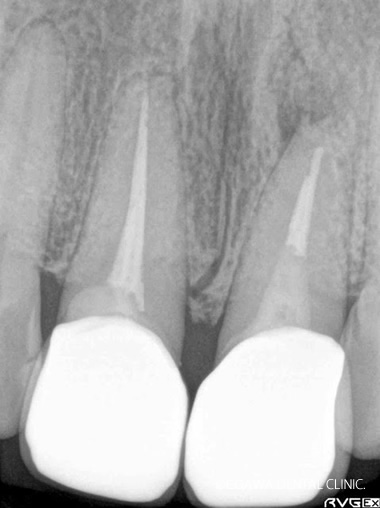

術前:レントゲン

術後:レントゲン

直接覆髄で歯髄を残せました(凹凸部分がMTAの箇所)

不幸にして歯髄治療を行わなければいけない場合、ファーストチョイスで直接覆髄を行いますが、直接覆髄でもダメなケースは根管治療を行います。まずは根管治療を行い、もし治らない場合は、根管治療は何度も続けるものではありません。その場合、後述でご紹介している歯根端切除術などの外科的な根管治療に移行します。その際、CTによる精密な診査・診断が必要となります。